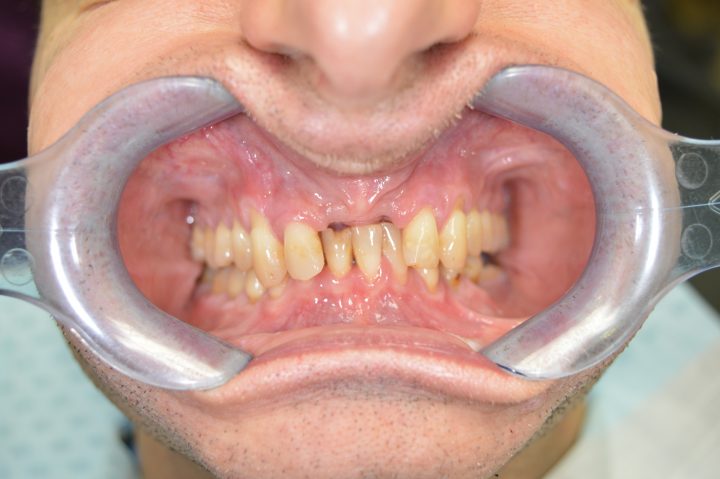

Chris

Chris ist ein 31-jähriger Engländer. Wegen dem unsystematischen Lebensstil und der nachlässigen Zahnreinigungsgewohnheit sind ein paar Zähne bis seinem 30. Geburtstag übrig, und sind in rettungslosem Zustand.

Als er die Klinik besucht hat, konnte nicht mehr essen, weil er immer unter Kieferschmerzen gelitten hat. Aufgrund von der CT-Aufnahme hat Frau. Dr. Erdélyi den Behandlungsplan erstellt. Die übrigen Zähne wurden aus dem Grund von einer großen Entzündung entfernen.

In der gleichen Behandlung hat er noch oben 4, und unten 6 Implantate bekommen, daneben hat er im Ablauf den 5 Tagen provisorischen Zahnersatz gekriegt.